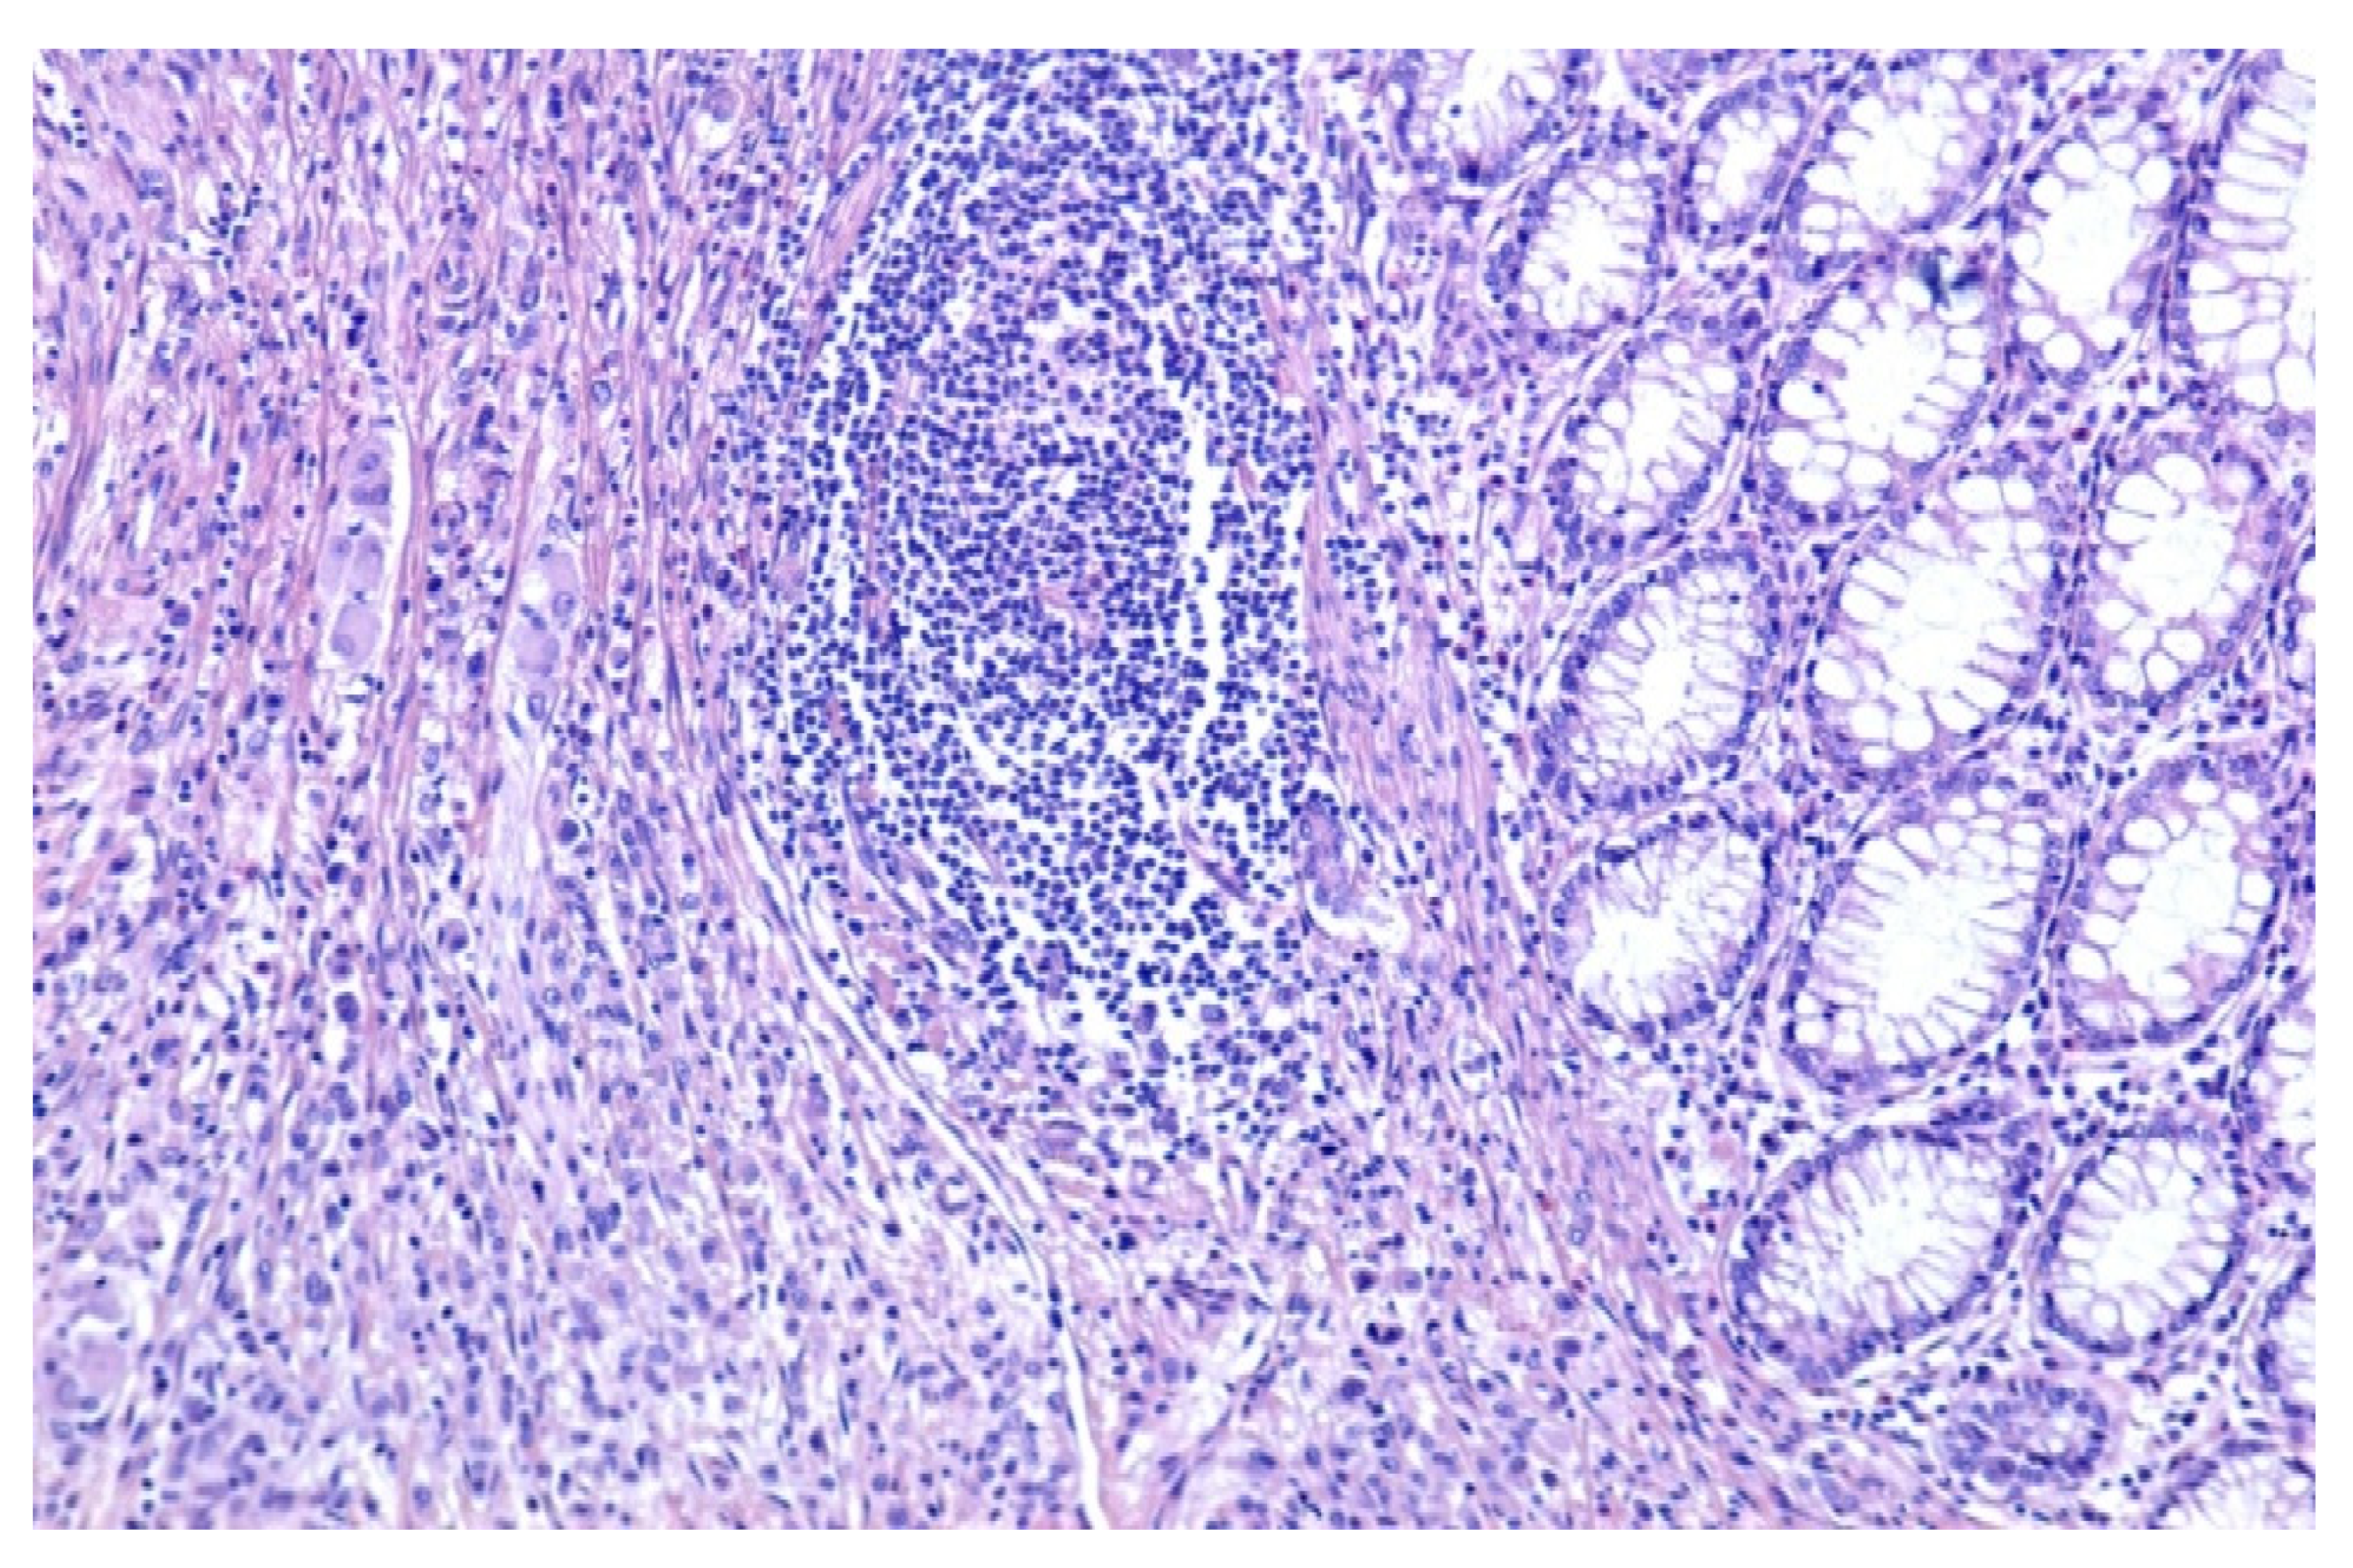

The histopathological diagnostic of the postoperator specimen (4394) was colonic malakoplakia as illustrated in Figure 2 and Figure 3.

Figure 2.

Colonic mucosa, which presents at the lamina propria level abundant mononuclear inflammatory infiltrate, predominantly macrophagic (HE, ×100).

The microscopic examination revealed:

- a significant architectural remodeling of the colonic mucosa and submucosa with dense cellular inflammatory infiltrate,

- the dense cellular inflammatory infiltrate-composed of epithelioid macrophages with wide eosinophilic cytoplasm, variable-sized nuclei, with occasional nucleoli,

- dispersed syncytia with the appearance of multinucleated giant cells, with chaotically disposed nuclei and

- amorphous cytoplasmatic inclusions of cellular detritus type, with sporadic intercalated lymphocytes.

Neither areas of necrosis, nor viable microorganisms were detected.

An area of ulcerated mucosa was identified, with reactive changes at the level of the remaining marginal epithelium.

Additionally, no invasive dysplastic or neoplastic stigmata were identified.